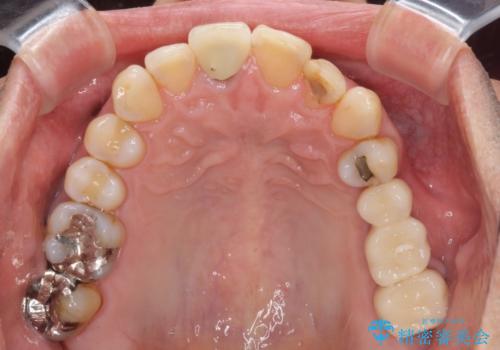

部分矯正期間中はアンカースクリューやフック、ゴムなどが粘膜にあたり、大変な思いをすることになりましたが、そのおかげでインプラント補綴した歯と最後方歯の位置が非常に良好となり、まるでご自身の歯のように咬むことができるようになりました。